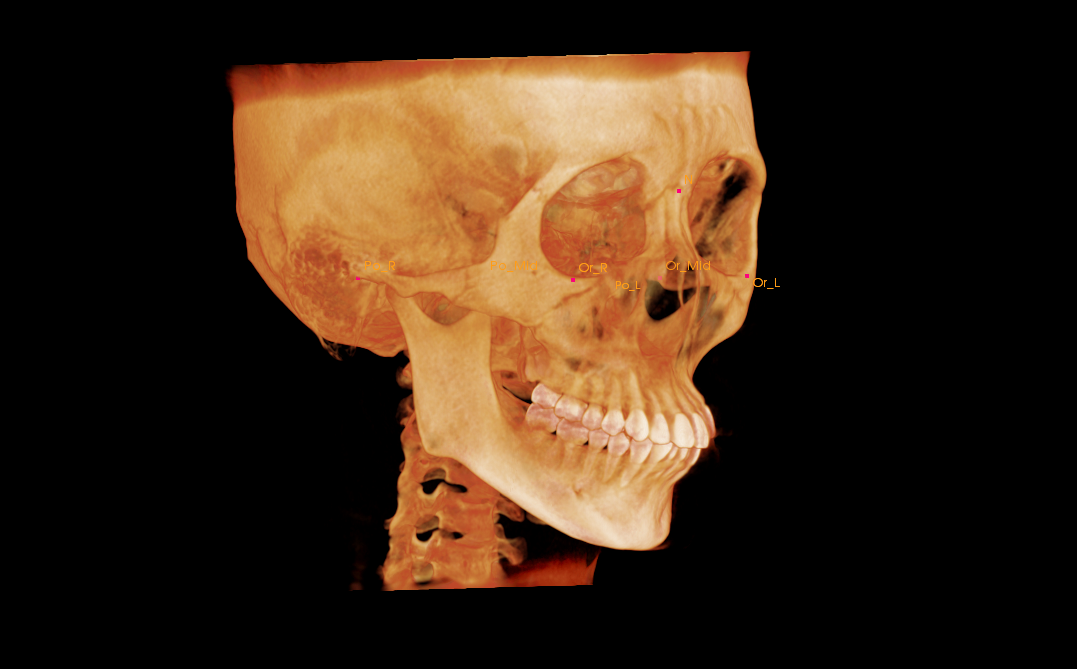

初診時の画像

結論から述べると、部分矯正だけで前歯のガタガタと出っ歯を両方とも治療するのはかなり困難です。前歯のガタガタの原因は歯の大きさと顎の大きさのバランスが悪いために前歯が綺麗に並ばないのです。顎を満員電車に例えると満員電車にさらに人が入ろうとしてぎゅうぎゅうになってしまっているのです。このような場合には①抜歯を行う、②歯を削って小さくする+歯並びを少し拡大するといった治療を行うことでガタガタを解消します。しかし、今回のように出っ歯もガタガタも気になる場合には、基本的には抜歯を行わなければ、歯を内に入れてガタガタを解消することができないのです。抜歯を行う場合は基本的には部分矯正では治療を行えませんので、今回K.Kさんの場合は全体の矯正治療が必要になります。

今回の症例では、前歯部の叢生および上顎前突を主訴に来院された患者様のご相談内容でした。